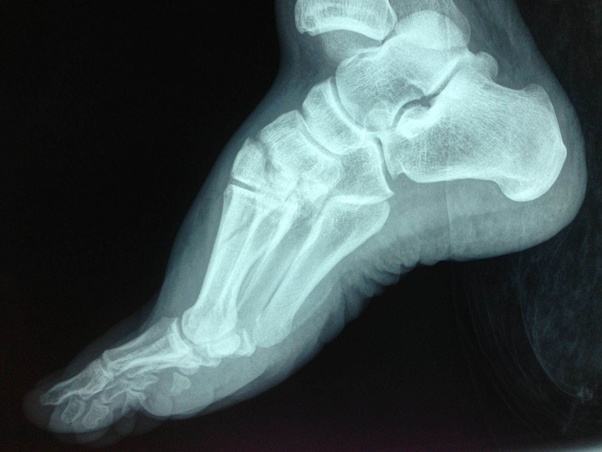

Throughout early childhood, this condition is not noticed. Accessory navicular bones are classified into three groups based upon shape and position (7). The navicular is an intermediate tarsal bone on the medial side of the foot, which articulates proximally with the talus. An accessory navicular is congenital (present at birth). An accessory navicular is an extra bone that is on the inner center arch of the foot. "we added bisphosphonate therapy to our treatment protocol, and within 30 days the horse had returned. Distally it articulates with the three cuneiform bones. This compression—along with the lack of blood supply to the navicular bone—increases the chances of … The tibialis posterior tendon inserts into the navicular bone. To better understand why it seems like one treatment works great for one horse and marginally for another, it is important to understand a little bit of the history of navicular syndrome, the anatomy that is involved, and available treatment options. The navicular bone is calcified in children when they are around 3 years old. It is incorporated within the posterior tibial tendon, which attaches in this area and can lead to accessory navicular syndrome. Up to 2.5 percent of individuals are born with the accessory navicular.

The navicular bone is calcified in children when they are around 3 years old. Sep 11, 2020 · navicular syndrome is a common condition, but it is not simple or straightforward. Throughout early childhood, this condition is not noticed. The navicular is an intermediate tarsal bone on the medial side of the foot, which articulates proximally with the talus. It is present from birth (congenital) and is a common trait.the reported incidence differs among populations and ethnic groups, and they are mostly reported as incidental findings in anatomical and imaging studies.